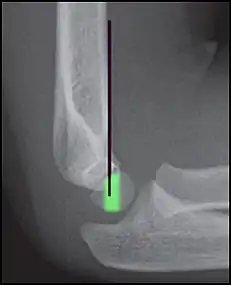

Anterior humeral line (black line), with normal area passed on the capitulum of the humerus colored in green in a 4 year old child.[9]